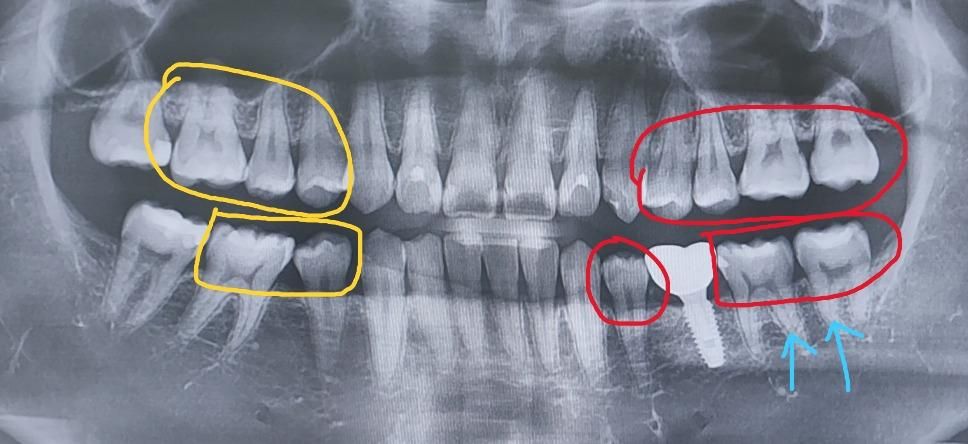

현재 만 24인 남성입니다. 최근에 치과진료를 하게되면서 사진과 같이 왼쪽 5개의 어금니 및 소구치를 인레이(지르코니아)로 치료진행을 하게 되었는데 치료를 진행하면서 느낀것이 인레이를 통한 비용도 한 몫 한 것도 있고, 사진상으로는 충치가 그렇게 많이 보이지 않아 과잉진료를 받았는 것인지 의문이 들어 질문을 작성하게되었습니다.

통상 치과 치료를 할 경우 검은 충치말고도 푸석푸석한 치아까지 다 제거를 하고 치료를 진행하는 걸로 알고있습니다. 그렇기에 이 변색되지 않고 푸석푸석한 치아는 사진상으로 밀도차이가 그렇게 나지 않는지가 궁금하고, 또 앞으로 빨간색 부분의 치과 치료(소구치는 인레이에서 레진으로 변경) 를 받을 것이지만 과잉진료를 최대한 피하기 위해 사진상으로는 충치가 많이 있는지 다른 치과 선생님들의 자문을 구하고자 사진을 올려봅니다. (경과를 지켜봐도 되는 치료 or 빠른시기 권장하는 치료)로 알려주시면 감사하겠습니다.

추가적으로 노란색 부분은 지르코니아 인레이로 치료가 되었습니다. 또한 파란색 화살표로 된 치아는 제가보기에도 검은색 충치가 안쪽까지 보여서 확실하다고 생각이 들었지만 다른 치아는 어떤 상태인지, 그냥 경과를 지켜보는게 좋은 것인지에 대한 답변을 해주시면 감사하겠습니다.

전체적으로 치아 사이에 충치가 약간씩잇고 치료도 많이 받으신거 같습니다. 파노라마 상으로도 빨간색 부분은 치아 사이에 충치가 잇어 보이고 파노라마 사진보다는 더 작은 사진을 찍어보면 충치가 더 자세히 보일것같습니다. 충치가 잇으면 인레이 치료를 하시는게 좋습니다.